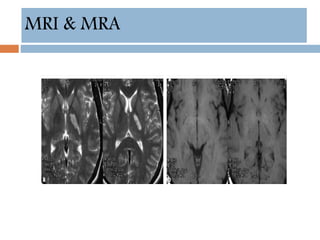

MRI & MRA